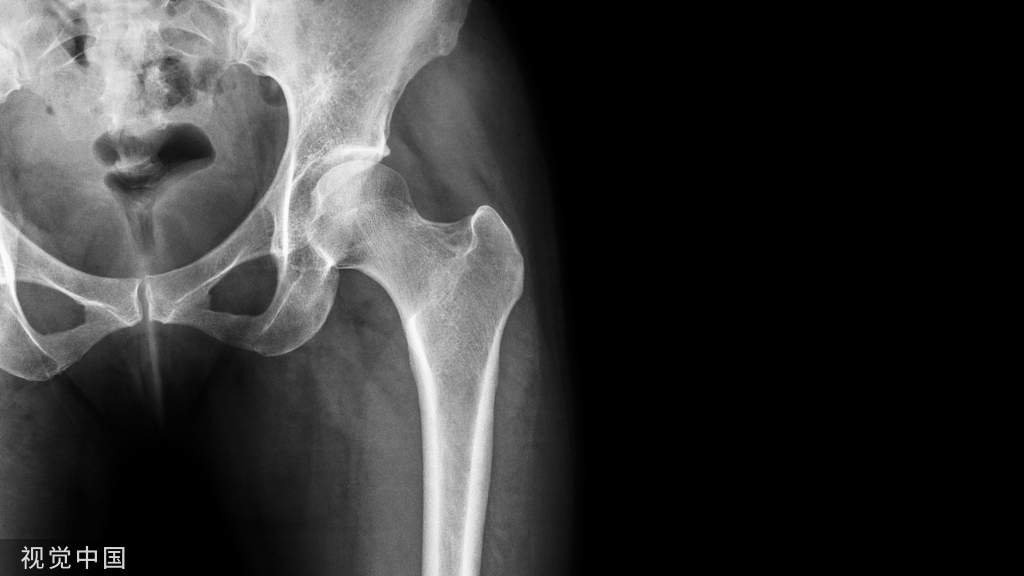

研究乳牙根管形态的方法有组织切片、镍钛锉探查、X线片、透明牙技术等,但均存在不足之处:组织切片样本量少,不够直观,来源困难;镍钛锉探查及X线平片具有不确定性,容易遗漏根管。

1、术前拍X片,了解尖周病变和牙根吸收情况。牙根吸收已达1/3以上者,难获良好的疗效。

5、术后应拍X片观察根充情况,分类: